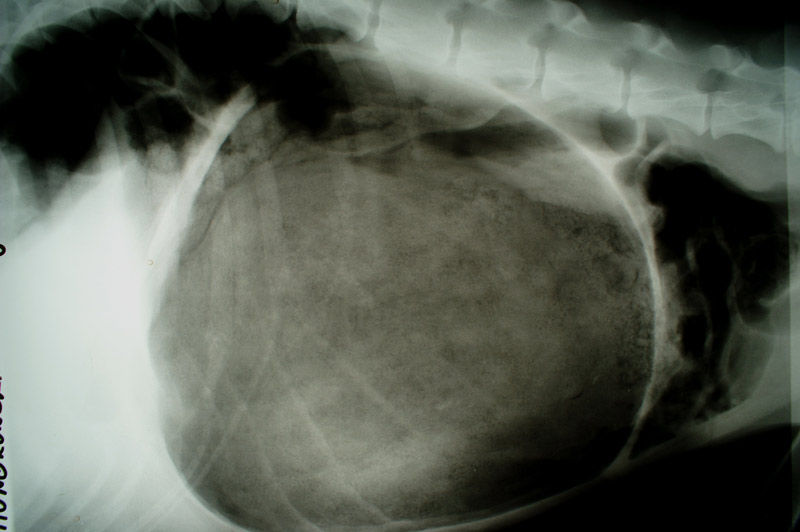

Magendrehung bei einem Dobermann

Aufgasung und Einziehung des Milz-Magenbandes